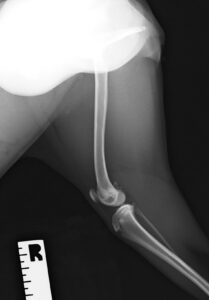

9ヶ月の柴犬の女の子が、高所から落下してしまい左後肢を痛めたとのことで来院されました。左後肢は足を着くことができず、レントゲン検査の結果、大腿骨(太ももの骨)の複雑骨折を認めました。

大腿骨の膝に近い部分が骨折してしまっており、さらに単純な骨折ではなかったため、内側と外側にそれぞれプレートを設置し固定しました。

大腿骨遠位の骨折は特に若齢の犬猫においてしばしば発生します。若齢時には多くの骨の両端に成長板という骨を作る場所があり、その場所は強い力がかかった際に骨折しやすいためです。単純な骨折の場合にはピンだけで整復が可能なことも多くありますが、今回のような状況ではプレート固定も適応になります。どちらにしても手術後に関節の拘縮が起きやすく、術後のリハビリも重要になってきます。当院ではリハビリに特化したスタッフも在籍し、術後のケアもご家族と共に実施していきますので安心して手術を受けて頂くことができます。